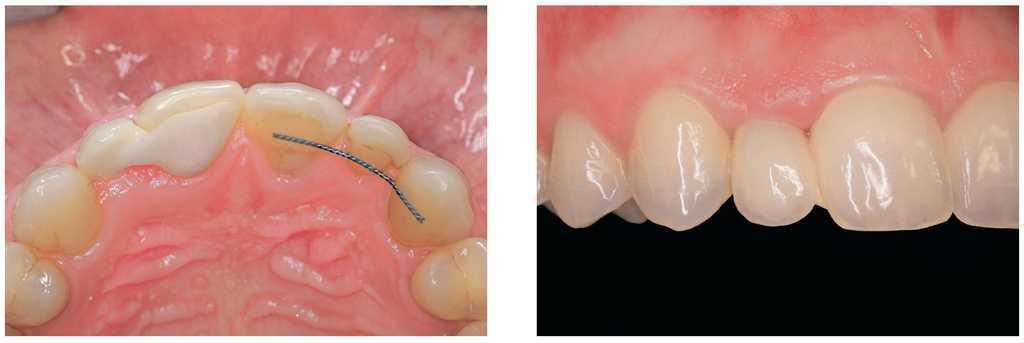

Figura 2a. Ausencia del diente 12, dientes adyacentes sin caries.

Figuras 2b y 2c. Puente adhesivo de cerámica sin metal de una aleta desde incisal (b) y vestibular (c).

Figura 3a. Ausencia del diente 22, dientes adyacentes restaurados con un tratamiento conservador.

Figuras 3b y 3c. Implante unitario con pilar (b) y corona unitaria (c).